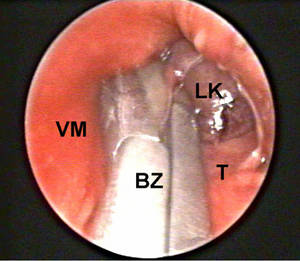

Im Röntgen des Brustkorbes kann die Verbreiterung oder Verlagerung des Mediastinums erkannt werden. Zur weiteren Abklärung ist eine Computertomographie (CT) (Abb.2), evtl. ergänzt durch eine Magnetresonanz-tomographie (MRT) oder eine Angiographie (Blutgefäßdarstellung), erforderlich. Zur genauen Diagnosestellung ist meist eine feingewebliche Untersuchung von Gewebsproben durch eine Punktion von außen oder über eine Bronchoskopie oder Ösophagoskopie notwendig.

Wenn es damit nicht möglich ist, eine sichere Diagnose zu stellen, besteht die Möglichkeit einer Mediastinoskopie (Spiegelung des Mediastinums) (Abb.2). Sehr selten ist eine Operation erforderlich.

Abb1: Gewebeentnahme durch Mediastinoskopie

LK = Lymphknoten, T = Trachea, AO = Aorta, WS = Wirbelsäule, BZ = Biopsiezange, VM = vorderes Mediastinum, PE = Pleuraerguß